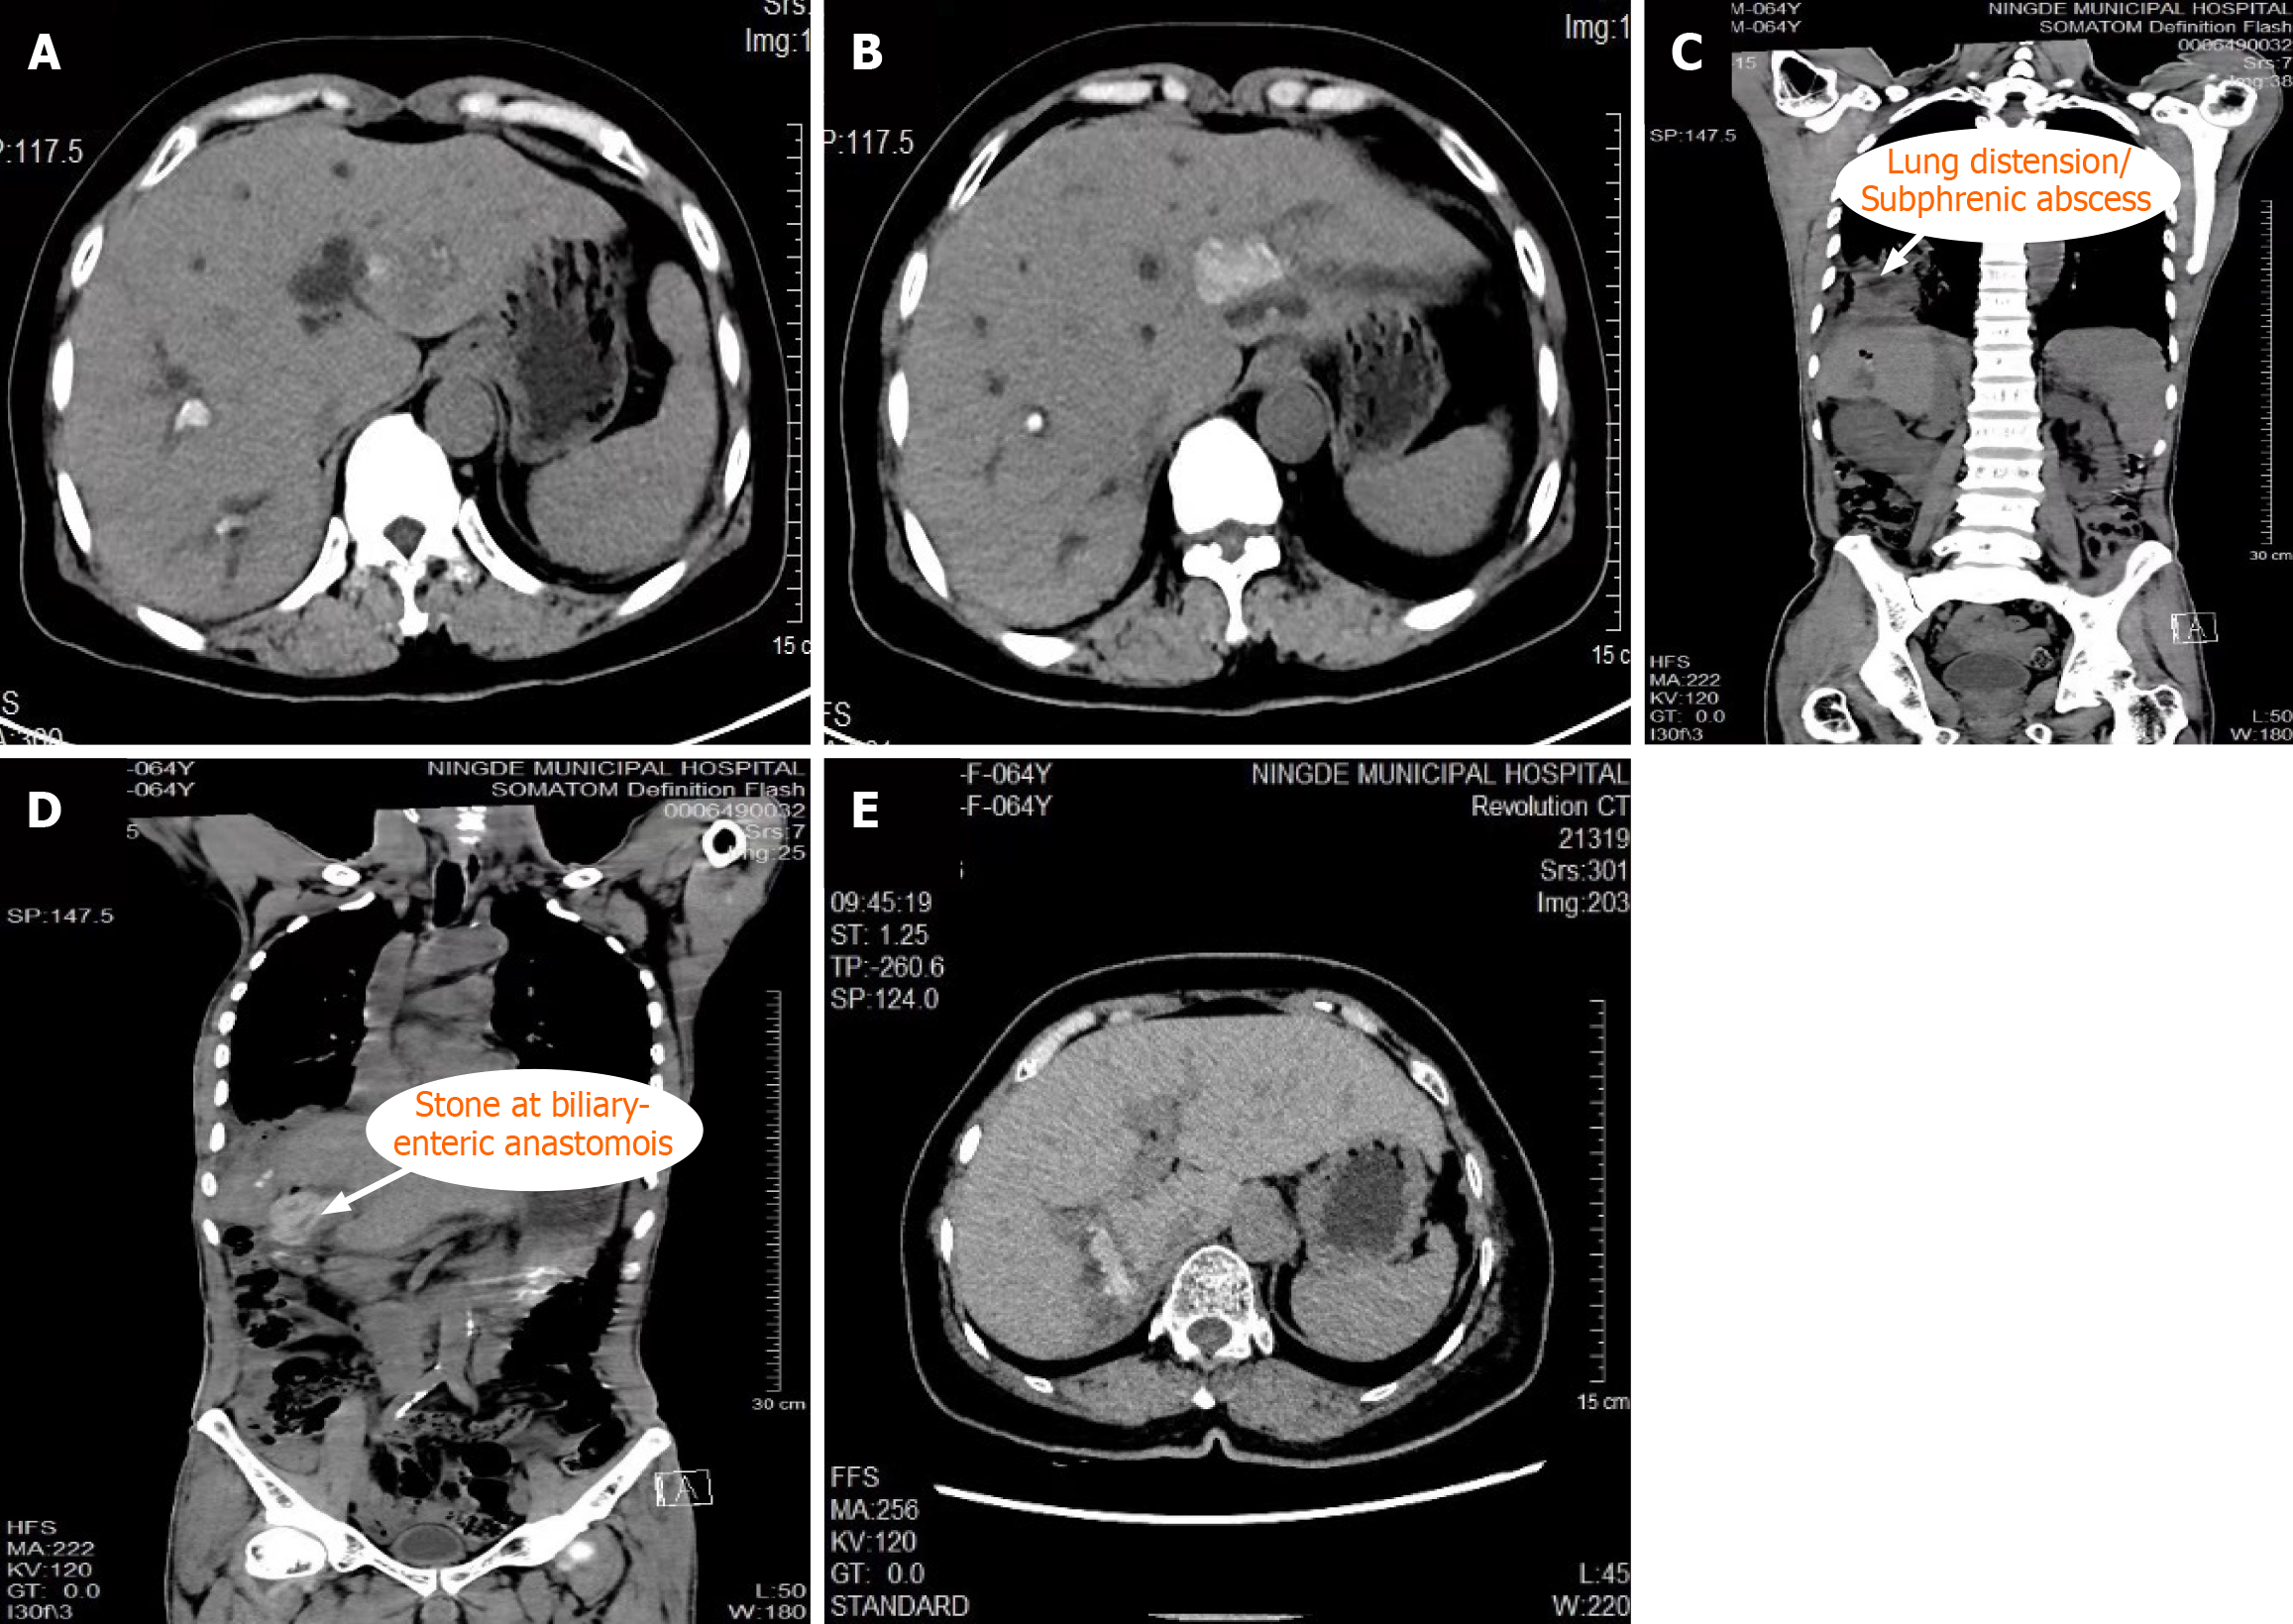

Figure 1 Preoperative images of selected cases with complex hepatolithiasis.

A and B: Preoperative axial and coronal computed tomography (CT) scans showing diffuse intrahepatic biliary stones in the left and right hepatic lobes; C: CT scan demonstrating lung expansion with subphrenic abscess secondary to recurrent cholangitis; D: CT scan showing a retained stone at the site of prior biliary-enteric anastomosis; E: CT scan revealing severe intrahepatic bile duct dilatation accompanied by parenchymal atrophy.